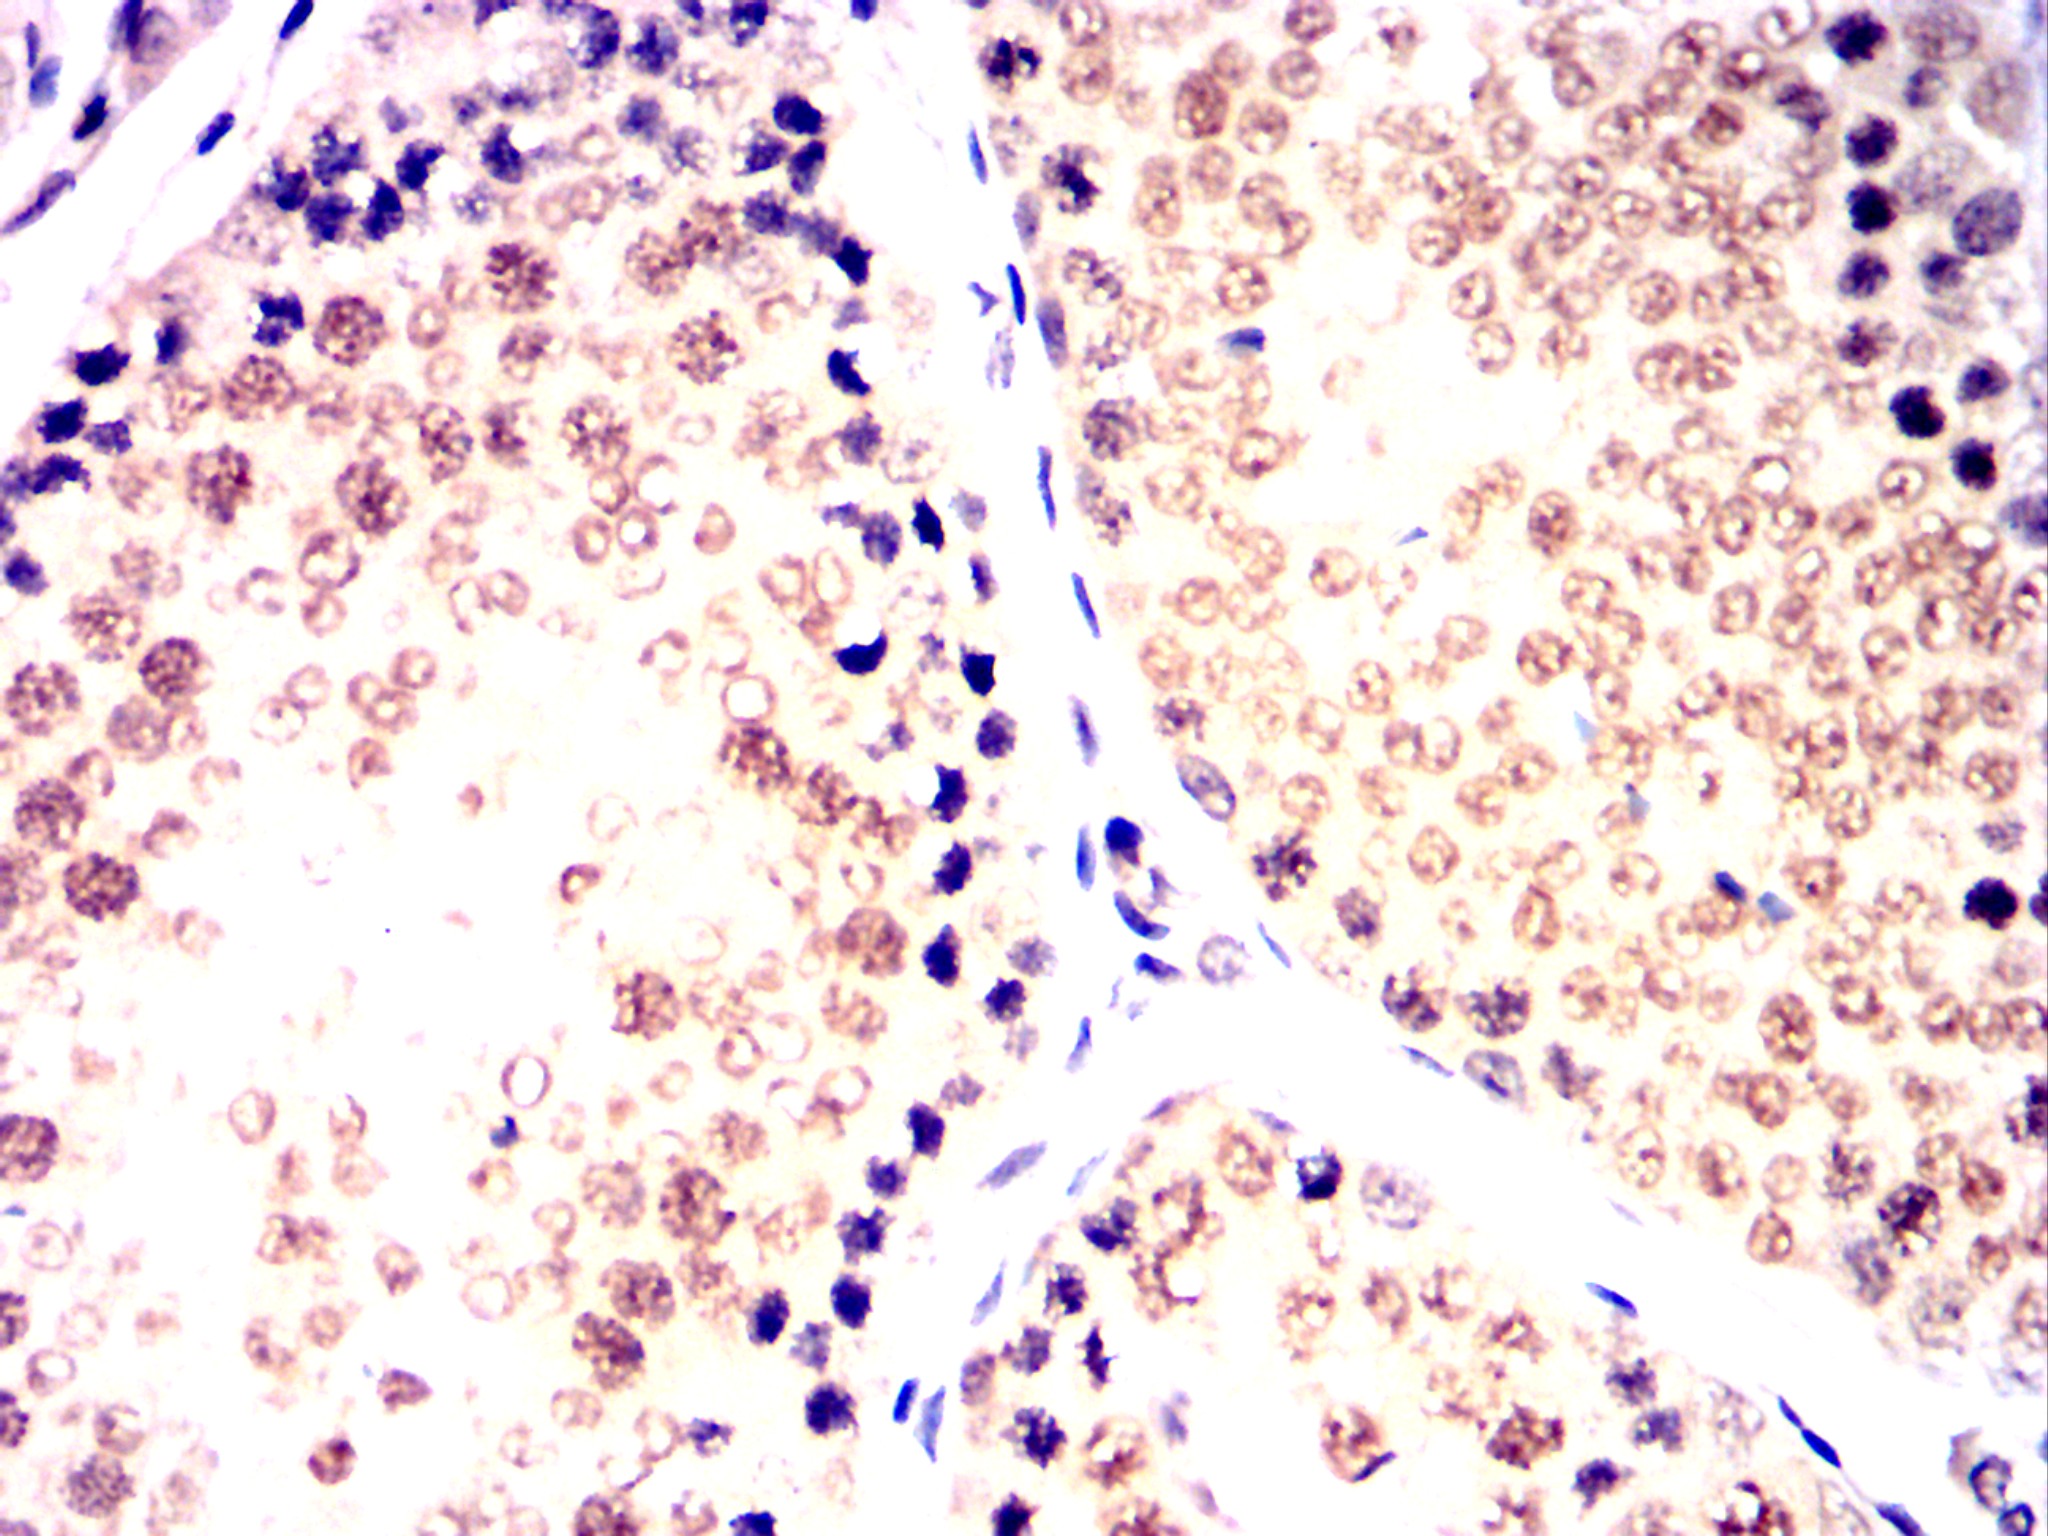

Immunohistochemical analysis of paraffin-embedded Mouse kidney using CDK9 mouse mAb with DAB staining.